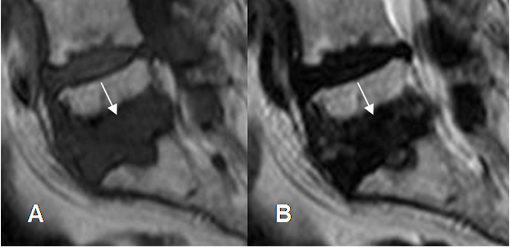

Fig 115. Nódulo de smorl.

A: RM axial en T1y B: RM sagital en T1. Defectos de bordes escleróticos en las placas terminales, por nódulos de smorl.